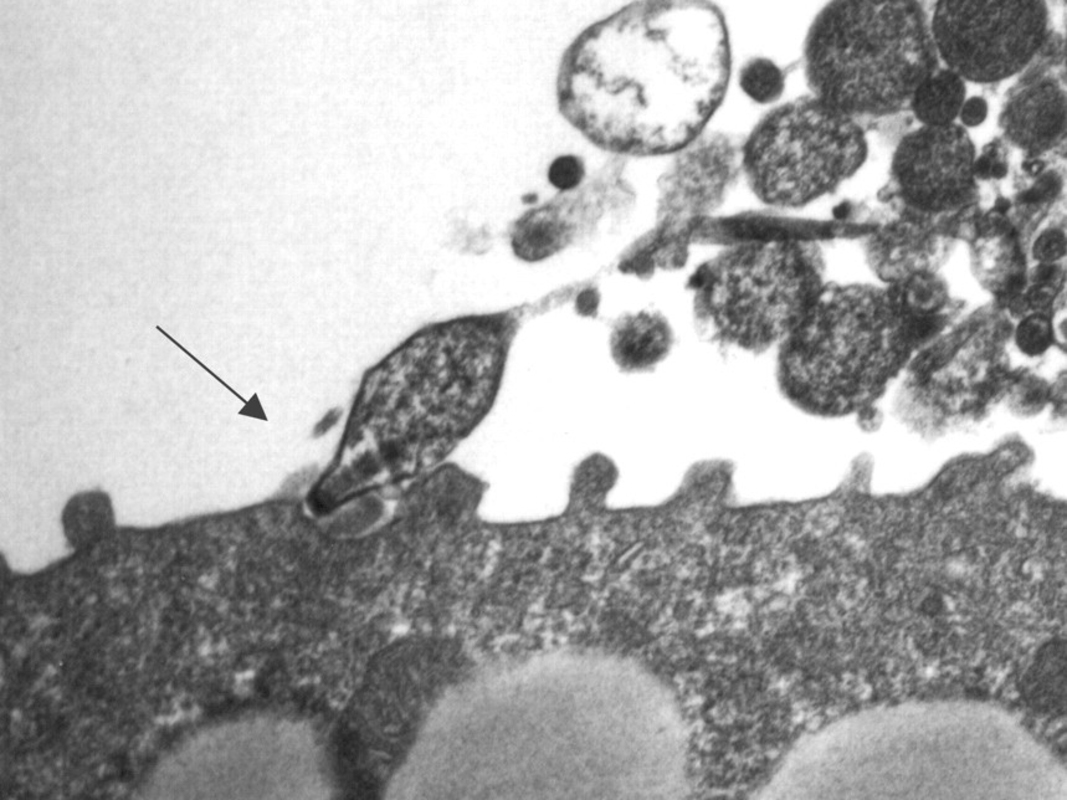

В отличие от других бактерий, Mycoplasma pneumoniae не может синтезировать многие липиды, необходимые для целостности своей мембраны, включая холестерин, и поэтому ее выживание полностью зависит от хозяина. В этом контексте новое исследование демонстрирует, что белок Р116 действует как высокоэффективная система поглощения липидов, способная извлекать холестерин и другие виды липидов как из липопротеинов человека, включая липопротеины низкой (ЛПНП) и высокой (ЛПВП) плотности, так и из различных типов клеток.

Эксперименты, проведенные авторами, показывают, что Р116 быстро поглощает холестерин из ЛПНП и ЛПВП, но также может захватывать фосфатидилхолины, сфингомиелины и триацилглицерины. Эта способность распознавать и поглощать различные типы липидов делает Р116 важным механизмом выживания микроорганизма. Снабжая свою мембрану компонентами, полученными непосредственно от хозяина, Mycoplasma pneumoniae может адаптироваться к различным условиям в организме и заселять ткани с высоким содержанием липидов за пределами дыхательной системы.

Исследование также показало, что моноклональные антитела, специфически направленные против С-концевого домена Р116, заметно блокируют поглощение холестерина бактерией, что является необходимым для ее выживания процессом. Предотвращая функционирование P116 в качестве системы поступления липидов, антитела значительно снижают рост Mycoplasma pneumoniae в клеточных культурах и ограничивает ее способность прикрепляться к атеросклеротическим поражениям человека в образцах ex vivo. Это двойное действие - замедление размножения бактерий и предотвращение их присутствия в уязвимых областях сердечно-сосудистой системы - представляет собой значительный прогресс в понимании патогенной роли этого микроорганизма.